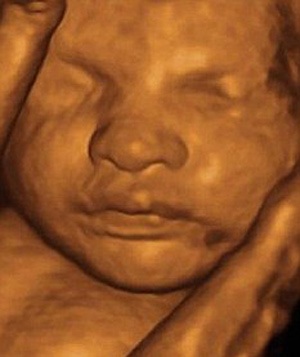

Có nên chụp ảnh thai nhi?

(Dân trí) - Các bậc cha mẹ được cảnh báo nên nghĩ kỹ về những nguy cơ có thể gặp phải khi sưu tầm những bức ảnh thai nhi như một kỷ niệm về giai đoạn bé ở trong tử cung người mẹ.

Khảo sát mới nhất tại Anh cho thấy: các bà mẹ tương lai thường có xu hướng chụp ảnh thai nhi hoặc ghi lại sự chuyển động của thai nhi vào đĩa CD hay DVD. Với công nghệ siêu âm 3D (3 chiều), những người ủng hộ cho rằng chúng đã tạo ra những bức ảnh sống động về những em bé còn trong bụng mẹ trong khi siêu âm 4 chiều lại giúp quan sát những cử động của thai nhi tại thời điểm soi.

Nhóm cố vấn độc lập của Tổ chức Bảo vệ sức khỏe (HPA) Anh cho rằng: “Có một số lo ngại về việc theo dõi sự phát triển của thai nhi qua máy siêu âm”. Sự lo ngại này ở chỗ: sóng siêu âm sẽ trực tiếp tác động lên đầu thai nhi khi thực hiện thao tác chụp ảnh, ghi hình. Một số nghiên cứu cho thấy sự liên quan của siêu âm nhiều với tỉ lệ thuận tay trái ở các bé trai.